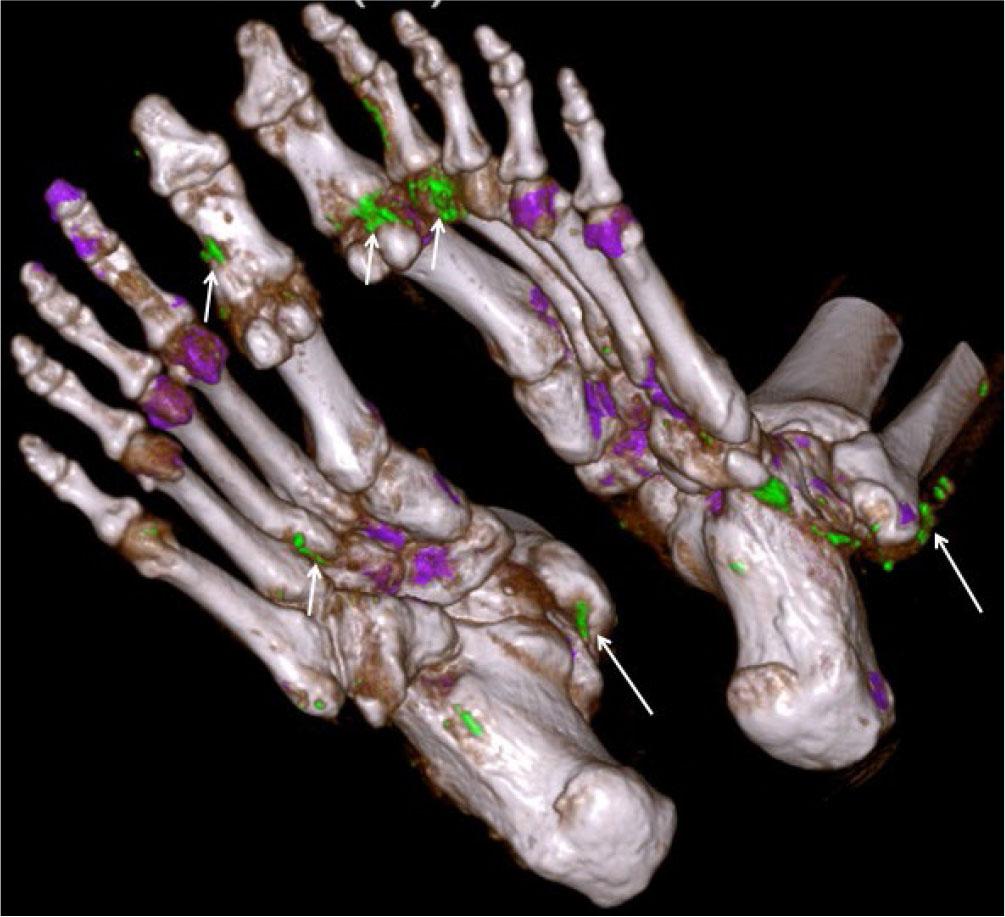

Dual-energy CT (DECT) employs simultaneous scanning using two energy sources of different X-ray energy levels (80 kV and 140 kV). Evaluation of the different attenuations of the scanned object allows analysis of the chemical composition of materials, which can be color-coded for visualization and then measured. By analyzing the differences in X-ray absorption between uric acid crystals and surrounding tissues, DECT can detect the presence and distribution of urate crystals in gout (Fig. 30). It can assess the volume of crystals and help in differentiating gout from other crystal deposition diseases.

Fig. 30.

Dual-energy CT (DECT) in gout: 3D reconstructed image of DECT of both feet in a patient with gout shows green color-coded crystal aggregates around the joints (small arrows) and along the tendons (long arrows)